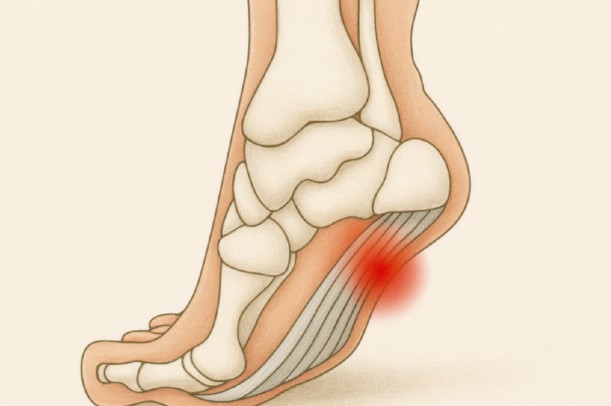

この症状の代表的な要因の一つに足底腱膜炎が挙げられます。足底腱膜はかかとから足指の付け根を結ぶ強靭な組織で、歩くときに土踏まずを支える役割を担っています。繰り返しの負担で炎症や微小な損傷が起こると、痛みにつながると説明されています(引用元:オムロンヘルスケア)。

足の裏の痛み、とくに土踏まずやかかとに響く痛みの代表例が足底腱膜炎だと言われています。足底腱膜が繰り返し引っ張られることで炎症や小さな損傷が生じ、朝起きて最初の一歩が強く痛むのが典型的なサインとされています(引用元:オムロンヘルスケア)。

土踏まずの痛みは、特に朝起きて最初の一歩で強く感じやすいと言われています。寝ている間に縮んだ足底腱膜が、体重をかける瞬間に引き伸ばされることで痛みが走ると考えられています(引用元:オムロンヘルスケア)。

- かかと寄りが痛い → 足底腱膜炎の可能性が高い

圧迫・動作での変化